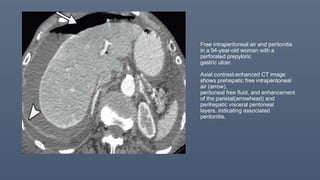

Free intraperitoneal air and peritonitis

in a 94-year-old woman with a

perforated prepyloric

gastric ulcer.

Axial contrast-enhanced CT image

shows prehepatic free intraperitoneal

air (arrow),

peritoneal free fluid, and enhancement

of the parietal(arrowhead) and

perihepatic visceral peritoneal

layers, indicating associated

peritonitis.